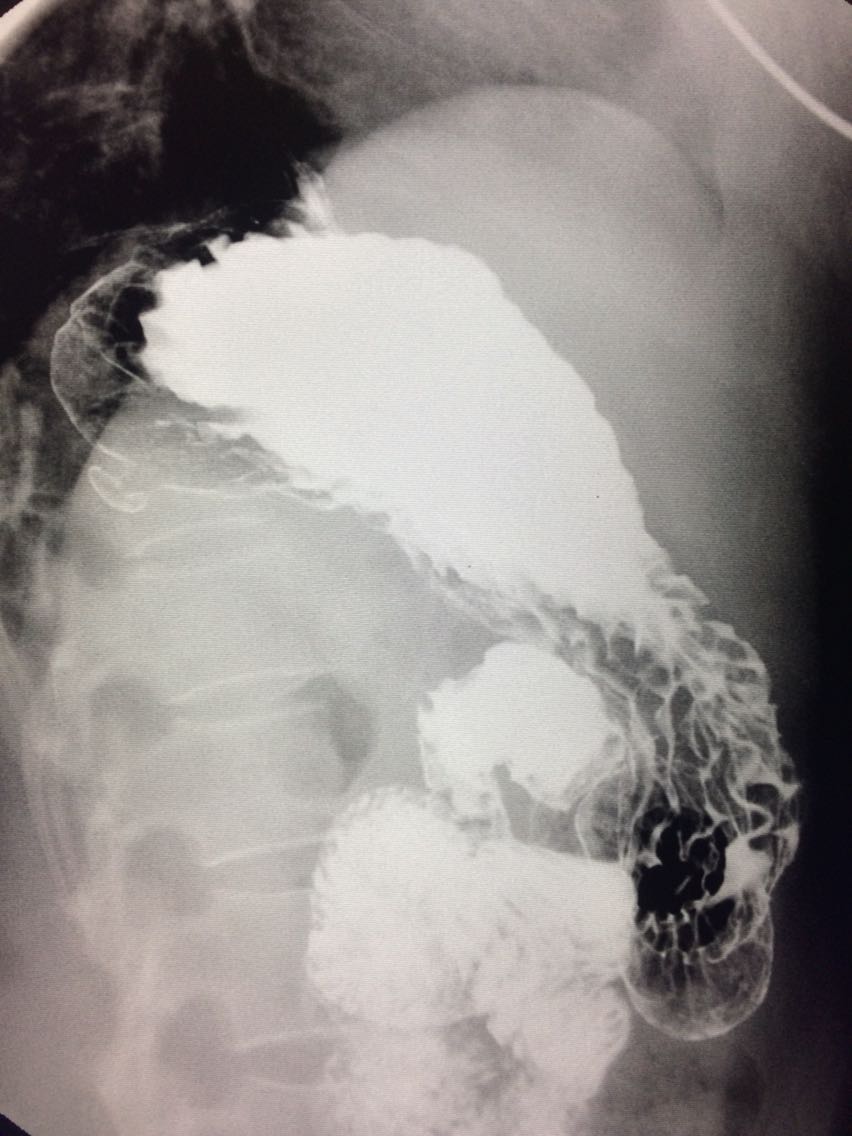

胃底憩室一例

女.47岁 体检来诊。 平素体健,无明显症状。 做上消化道造影如图。

诊断,胃底憩室。 治疗,患者无明显症状,未予治疗。